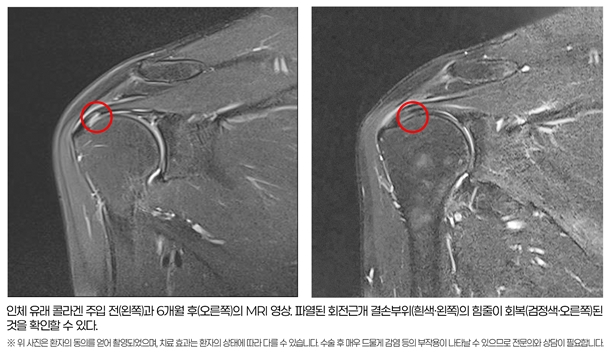

À̹ø ¿¬±¸ÀÇ °¡Àå Å« ¼º°ú´Â MRI¸¦ ÅëÇØ ÈûÁÙÀÇ ±¸Á¶Àû ȸº¹À» Á÷Á¢ È®ÀÎÇß´Ù´Â Á¡ÀÌ´Ù. 6°³¿ù ÈÄ MRI ºÐ¼® °á°ú, ȸÀü±Ù°³ ¼Õ»ó ÁöÇ¥ÀÎ ½ÅÈ£°µµÀÇ È£Àü ¹× ÆÄ¿ ºÎÀ§ÀÇ Àç»ýÀÌ 1mmÀÌ»ó ³ªÅ¸³ ȯÀÚ°¡ 83.33%(25/30¸í)¿¡ ´ÞÇß´Ù. ÆÄ¿ ºÎÀ§°¡ 2mmÀÌ»ó °¨¼ÒÇÑ È¯ÀÚµµ 26.66%(8/30¸í)¸¦ Â÷ÁöÇß´Ù. ¶ÇÇÑ ½ÉÇÑ ¿°ÁõÀ» ³ªÅ¸³»´Â ü¾×Àú·ù Çö»óÀÌ È¯ÀÚÀÇ Àý¹Ý ÀÌ»óÀÎ 53.55%(16/30¸í)¿¡¼ À¯ÀǹÌÇÏ°Ô °¨¼ÒÇß´Ù. ÀÌ´Â Åë°èÀû À¯ÀǼº(p<0.05)À» È®º¸ÇÑ °á°ú·Î, Äݶó°Õ ÁÖÀÔ¼úÀÌ ÈûÁÙÀÇ Á¶Á÷ Àç»ýÀ» µ½°í ¼Õ»ó¿¡ ÀÇÇÑ ¿°ÁõÀ» ¿ÏÈÇÏ¸ç ÆÄ¿ÀÇ Å©±â¸¦ ÁÙÀ̴µ¥ È¿°ú°¡ ÀÖÀ½À» ½Ã»çÇÑ´Ù.